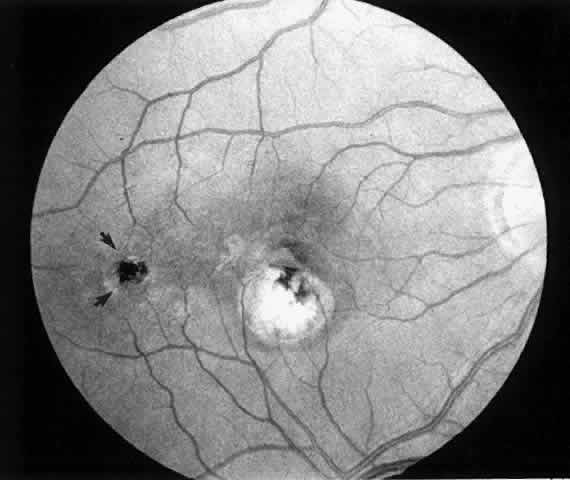

2. A 35-year-old patient developed an idiopathic subfoveal choroidal neovascular membrane with decrease in vision to 20/200 (6/60) (Fig. 9). He underwent surgical excision of the membrane. Laser was applied to the retinotomy at the conclusion of the case. One year after surgery, his visual acuity remained stable at 20/20 (6/6) (Fig. 10).

Fig. 9. Preoperative fundus photograph of a 35-year-old patient with idiopathic subfoveal neovascularization (case 2). Visual acuity is 20/200 (6/60).

Fig. 10. Postoperative fundus photograph (case 2). One year after surgery, visual acuity is 20/20 (6/6). Note laser scar at retinotomy site (arrows).